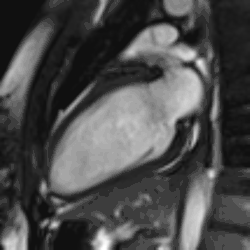

Atrial septal defect with dilation of the right ventricle by CMR

Heart function using cine imaging

Functional and structural information is acquired using bSSFP cine sequences. These are usually retrospectively-gated and have intrinsically high contrast in cardiac imaging due to the relatively high T2:T1 ratio of blood compared to myocardium. Images are typically planned sequentially to achieve the standard cardiac planes used for assessment. Turbulent flow causes dephasing and signal loss allowing valvular disease to be qualitatively appreciated. The left ventricular short axis cines are acquired from base to apex and are used for quantifying end-diastolic and end-systolic volumes, as well as myocardial mass. Tagging sequences excite a grid pattern that deforms with cardiac contraction allowing strain to be assessed.